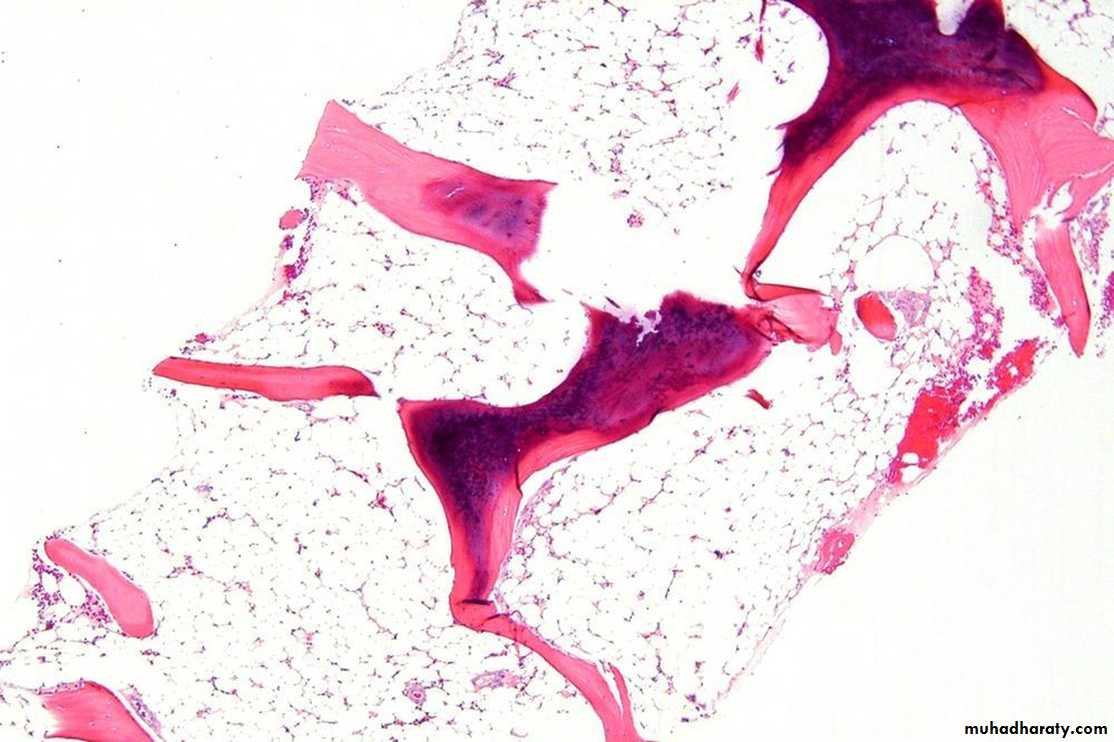

Bone marrow exam

A bone marrow aspirate & biopsy is performed. Both of them are hypocellular.A core biopsy is the most important and provides a better idea of cellularity; the specimen is considered hypocellular if it is less than 30% cellular in individuals younger than 60 years or less than 20% in those older than 60 years.

2. decreased marrow cellularity (< 25%)

- increased fat cells component

- no extensive fibrosis (vi)